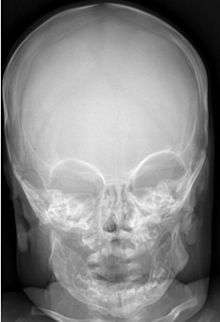

Most infants with infantile cortical hyperostosis are diagnosed by physical examination. X-rays can confirm the presence of bone changes and soft tissue swelling. Biopsy of the affected areas can confirm the presence of typical histopathological changes. No specific blood tests exist, but tests such as erythrocyte sedimentation rate (ESR) and alkaline phosphatase levels are often elevated. A complete blood count may show anemia (low red blood cell count) and leukocytosis (high white blood cell count). Other tests may be done to help exclude other diagnoses. Ultrasound imaging can help diagnose prenatal cases.

Radiographs initially show layers of periosteal new bone formation with cortical thickening. Periosteal new bone may cover the diaphysis of the bone, causing an increase in diameter of the bone. Over time, the periosteal new bone density increases, becoming homogenous with the underlying cortex. Eventually the bone remodels and resumes a normal appearance.